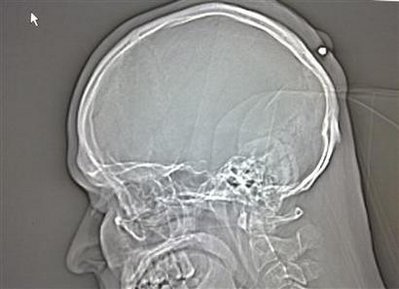

An X-ray released by German police August 24, 2010, shows a bullet lodged in the back of the head of a man. [Agencies]?

BERLIN – A Polish man living in Germany went about his business for about five years without noticing he had been shot in the head because he was drunk when it happened. Police in the western city of Bochum said on Tuesday doctors found a .22 caliber bullet in the back of his head after the 35-year-old went to have what he thought was a cyst removed.

Presented with the 5.6mm projectile, the man recalled he had received a blow to the head around midnight at a New Year's party "in 2004 or 2005," but had forgotten about it because he had been "very drunk," a police spokesman said.

The wound later healed around the bullet and it was not until the man decided to have the lump examined due to recurring pains that the discovery was made.